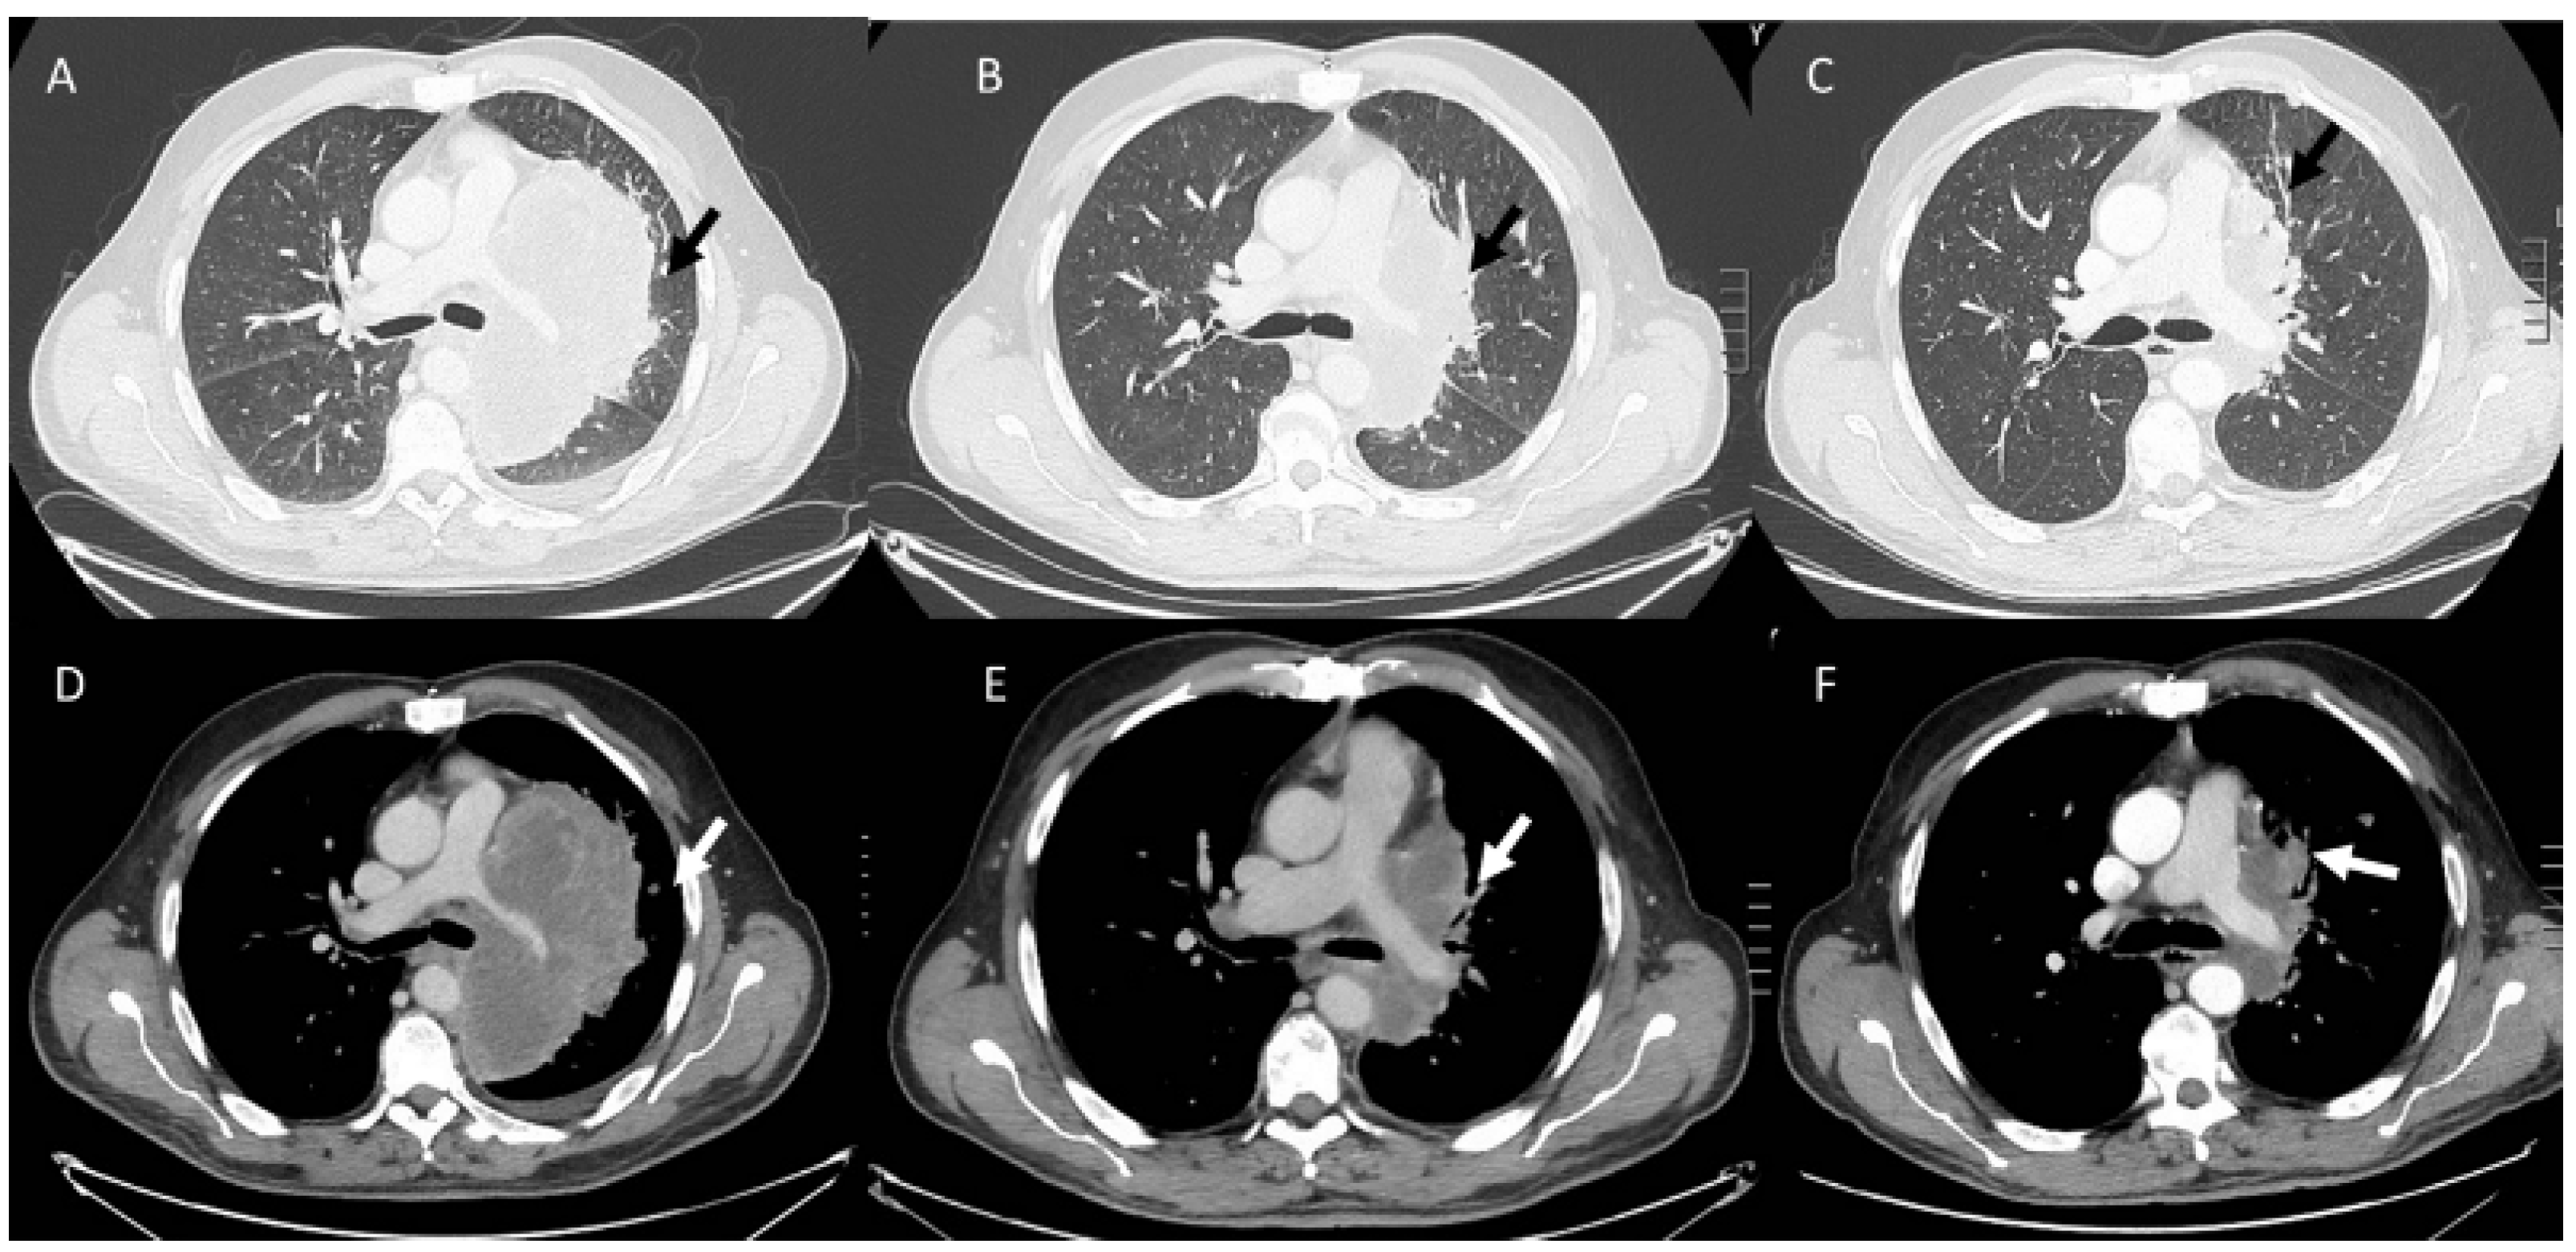

- Kalisz, K.R.; Ramaiya, N.H.; Laukamp, K.R.; Gupta, A. Immune Checkpoint Inhibitor Therapy-related Pneumonitis: Patterns and Management. Radiographics 2019, 39, 1923–1937. [Google Scholar] [CrossRef] [PubMed]

- Wang, G.X.; Kurra, V.; Gainor, J.F.; Sullivan, R.J.; Flaherty, K.T.; Lee, S.I.; Fintelmann, F.J. Immune Checkpoint Inhibitor Cancer Therapy: Spectrum of Imaging Findings. Radiographics 2017, 37, 2132–2144. [Google Scholar] [CrossRef]

- Kwak, J.J.; Tirumani, S.H.; Van den Abbeele, A.D.; Koo, P.J.; Jacene, H.A. Cancer immunotherapy: Imaging assessment of novel treatment response patterns and immune-related adverse events. Radiographics 2015, 35, 424–437. [Google Scholar] [CrossRef]

- Tirumani, S.H.; Ramaiya, N.H.; Keraliya, A.; Bailey, N.D.; Ott, P.A.; Hodi, F.S.; Nishino, M. Radiographic profiling of immune-related adverse events in advanced melanoma patients treated with ipilimumab. Cancer Immunol. Res. 2015, 3, 1185–1192. [Google Scholar] [CrossRef]